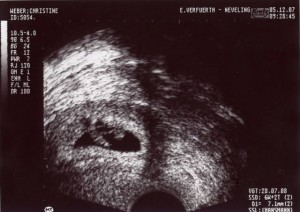

Mama und Papa haben mir freundlicherweise Bilder von meiner Ein-Zimmer-Wohnung zur Verfügung gestellt. Erstellt wurden die mit so einem Ding namens Ultraschall. Ich weiß nur noch, dass ich in den ersten Wochen von dem Teil überhaupt nicht begeistert war und mich immer ganz klein gemacht habe, wenn Mama und Papa schon wieder knippsen wollten. Aber wer lässt sich schon gern freiwillig in seine Privatsphäre schauen?

Hier ist bin ich schon etwas größer – 7mm.